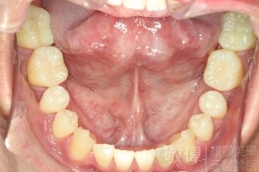

變臉矯正,原來戽斗妹跟大歪臉變成自信正妹

經由本院3D數影X光影像儀分析、與3D齒顎顏矯正技術,再配合口腔顎面正顎專科醫師施以正顎手術治療,雙方共同合作,使患者臉部外觀有很好的改善,大歪變小歪,產生了天南地北的大改變,她的人生也整個變得不一樣。

因為矯正與正顎手術的配合,使「戽斗妹」變成了「陽光正妹」,完全的改變了她的人生,在面對各種場合、與人交際都散發出自信微笑。所以,奉勸家長,如果小朋友有臉顎畸型的問題,應該考慮配合做這種簡單、安全、有效的正顎手術。